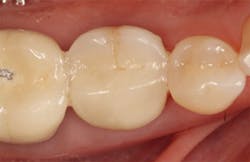

Stage II uncovering was performed five months following the initial surgery. A crestal incision was made toward the lingual ridge to split the keratinized gingiva, as that is where the keratinized gingiva had settled following surgery due to the coronal advancement of the buccal flap to obtain primary closure. The keratinized gingiva was buccally positioned, and a healing abutment was placed. The tissue was sutured with 4.0 chromic gut. This allowed the attached gingiva to heal on the buccal portion of the healing abutment and thus remain on the buccal portion of the final restoration. Final impressions were taken two weeks later, and the restoration was delivered thereafter.

The patient returned three and six months later for a postdelivery radiograph and healing check. The peri-implant tissues were healthy with no abnormal bleeding or probings. The patient reported high satisfaction with his new implant restoration.